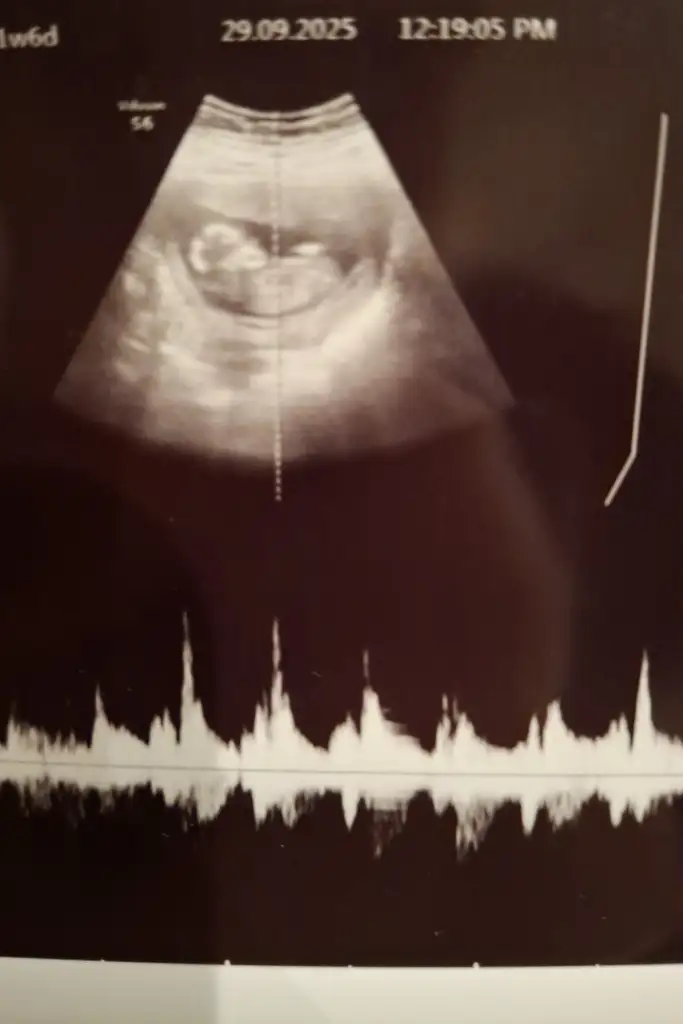

Nub teorisi cinsiyet tahmini

Bana da bakar mısınız 12+4 haftalık

Merhaba cinsiyet tahmini yaparmısınız kızlar🌸